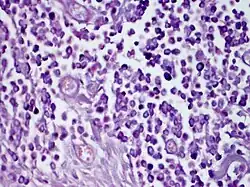

| Solitary mastocytoma. | |

Based on the lesion's shape, the existence of a positive Darier sign, and the lack of systemic involvement, the diagnosis is primarily clinical.[19] If necessary, a skin biopsy can be used to confirm the diagnosis by demonstrating a KIT mutation in the lesional skin and confirming mast cell infiltration in the dermis.[2]